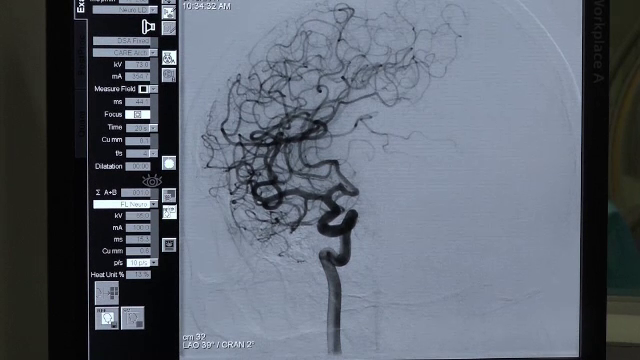

Intervenţie în premieră în România: o pacientă cu 7 anevrisme cerebrale a primit o nouă șansă la viață

Intervenţie a avut loc la Spitalul Judeţean de Urgență din Târgu Mureș. O femeie de 54 de ani a primit o nouă ...